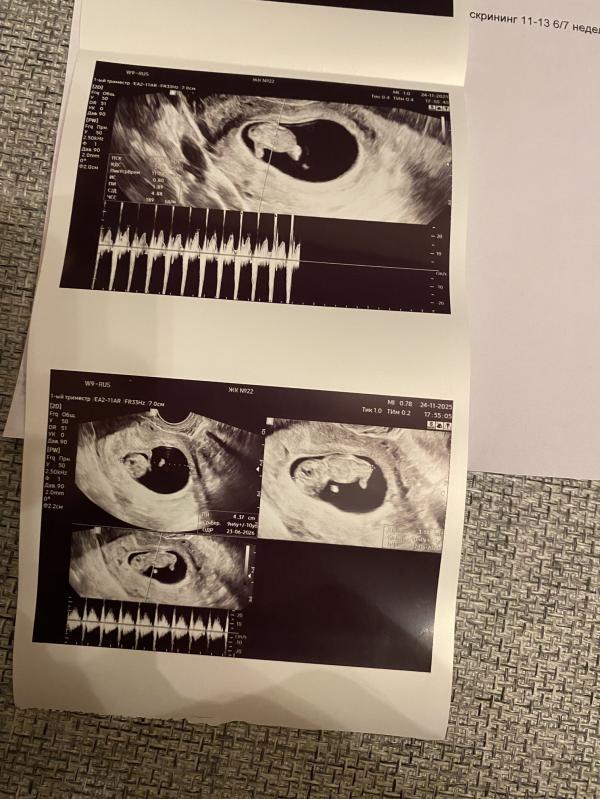

УЗИ 10 недель

Высокое сердцебиение плода (189 ударов) на фоне активных шевелений.

Сегодня ходила платно.

Завтра день рождения у мамы молодого человека и мне захотелось сообщить красиво - со снимками, а то на обычных приёмах ничего не распечатывают и не особо многословны. А тут всё рассказали, с разных сторон показали.